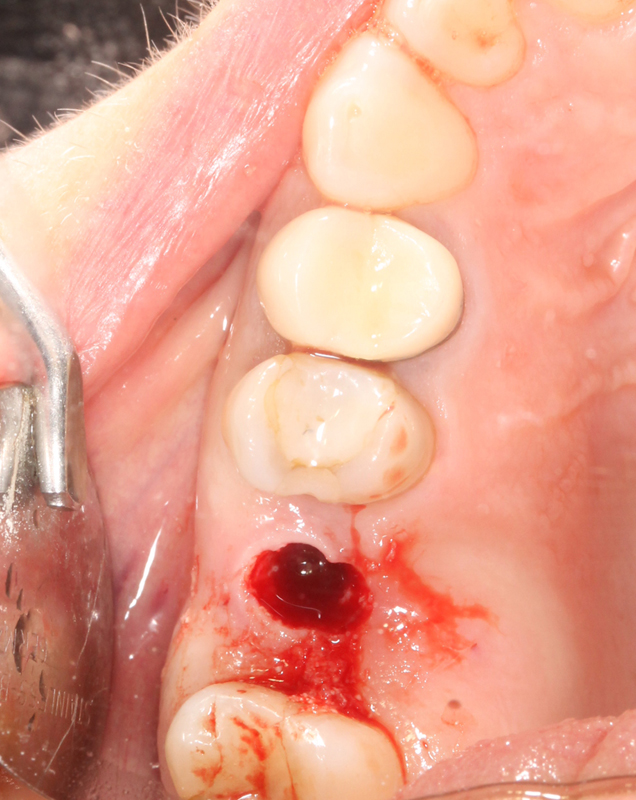

A distanza di 12 mesi viene inserito un impianto Tissue Level Straumann in sede molare superiore, con tecnica Flapless Modificata.

La paziente rimane soddisfatta del minimo disaggio post-operatorio.